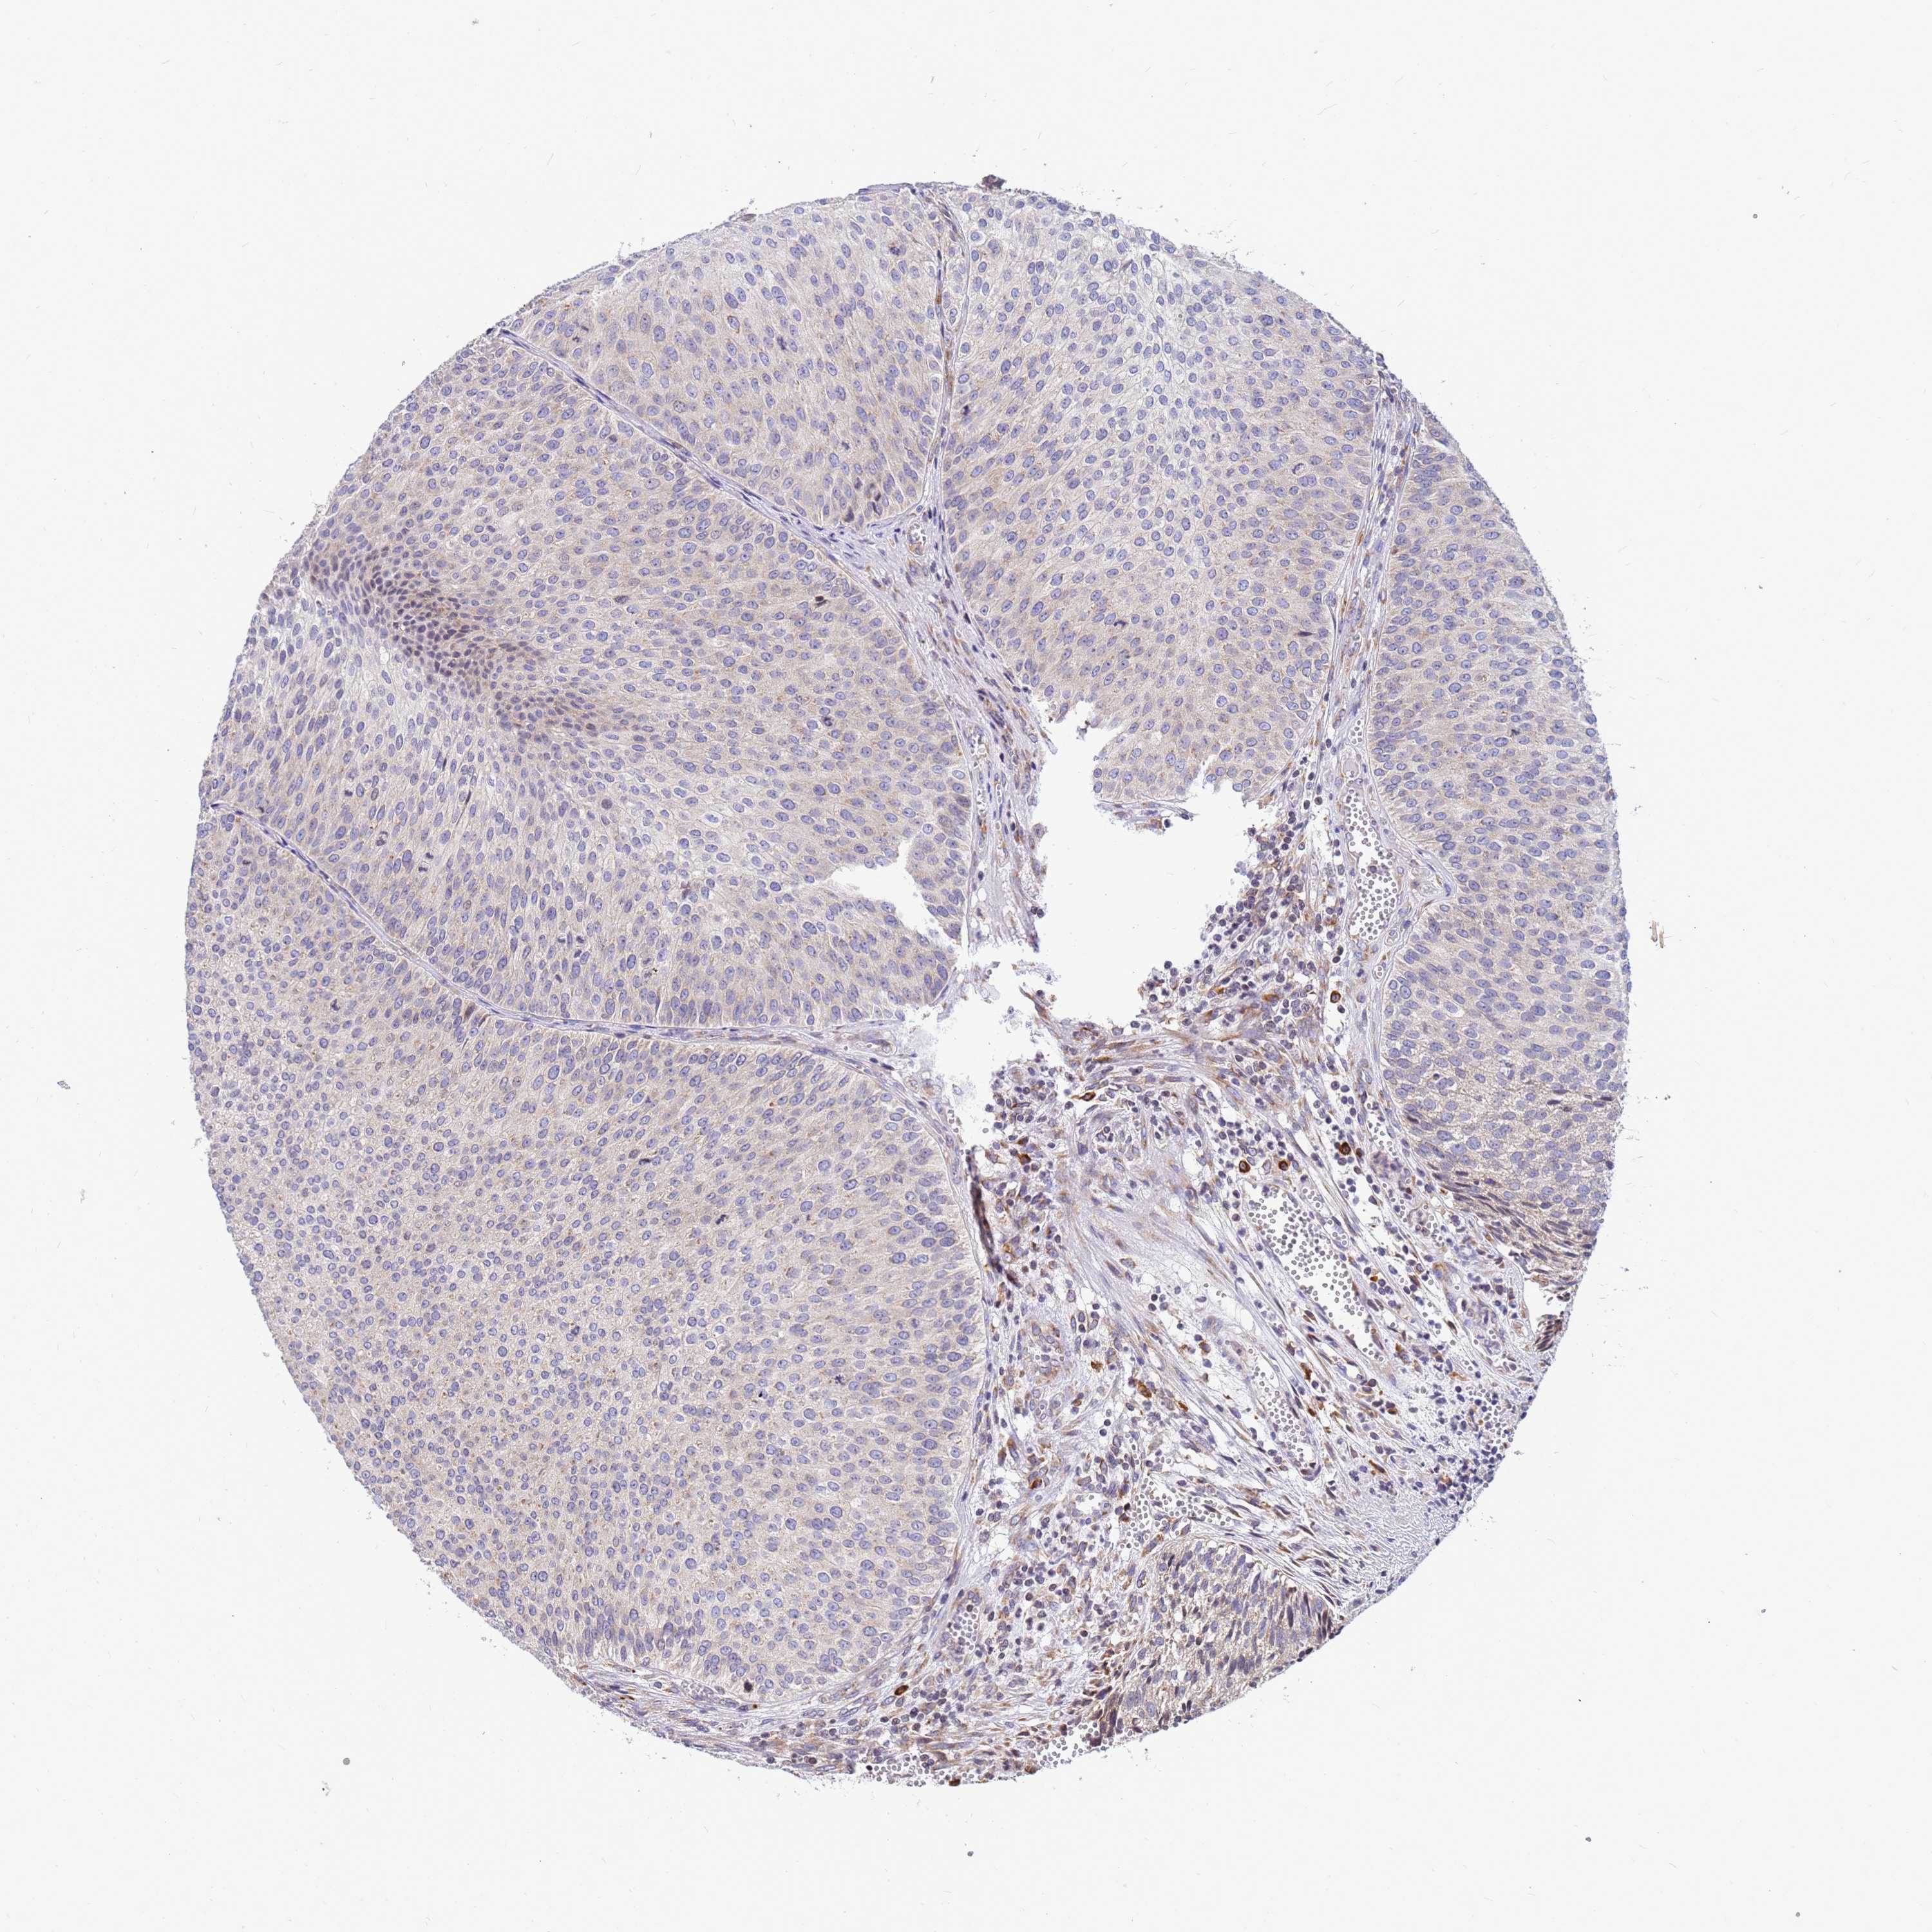

UROTHELIAL CANCER - Protein expressioni

A mouse-over function shows sample information and annotation data. Click on an image to view it in a full screen mode. Samples can be filtered based on level of antibody staining by selecting one or several of the following categories: high, medium, low and not detected. The assay and annotation is described here.

Note that samples used for immunohistochemistry by the Human Protein Atlas do not correspond to samples in the TCGA dataset.

Antibody stainingi

Antibody staining in the annotated cell types in the current human tissue is reported as not detected, low, medium, or high, based on conventional immunohistochemistry profiling in selected tissues. This score is based on the combination of the staining intensity and fraction of stained cells.

Each image is clickable and will lead to virtual microscopy that enables deeper exploration of all samples and also displays staining intensity scores, fraction scores and subcellular localization as well as patient and tissue information for each sample.

Antibody HPA045209

Staining

High

Medium

Low

Not detected

Intensity

Strong

Moderate

Weak

Negative

Quantity

>75%

75%-25%

<25%

None

Location

Nuclear

Cytoplasmic/membranous

Cytoplasmic/membranous,nuclear

Urothelial carcinoma, Low grade